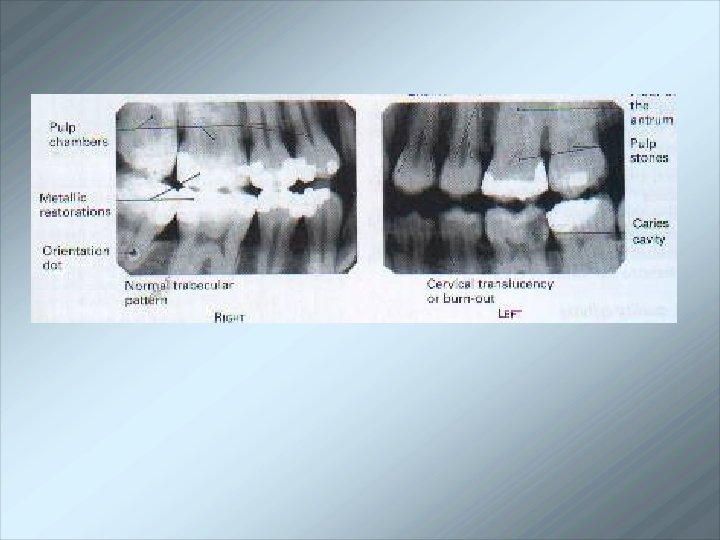

Bitewing radiography is that intraoral technique which allows the clinicians to evaluate initial lesions by passing the primary ray perpendicular to the long axis of the respective teeth

Indications for bitewing technique: In the diagnosis of interproximal caries. Detection of secondary caries under the restoration. To study the height of the pulp chamber. To check the health of inter-dental alveolar bone in health and periodontal disease. In the diagnosis of pulp stone. To study occlusion of the teeth. To detect calculus deposits in inter-dental areas. To determine if restoration is fractured. Relationship of deciduous to the permanent teeth in children with mixed dentition.